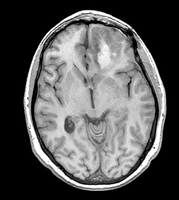

• inner part of the tumor segmented from SPGR

• outer part of the tumor segmented from post-Gad

• WM and GM segmented from N4-processed SPGR (WM segmentation of the original SPGR volume is included, note under-segmented WM in the skull base)

• all segmentations were done using FastMarching, fiducials are included for each of the segmentations

• no fine-tuning of the fiducial locations was done -- this is an example result one can get almost right away

• rule of thumb in placing fiducials: try to cover uniformly the volume you are trying to segment; this is particularly important for large structures like WM/GM